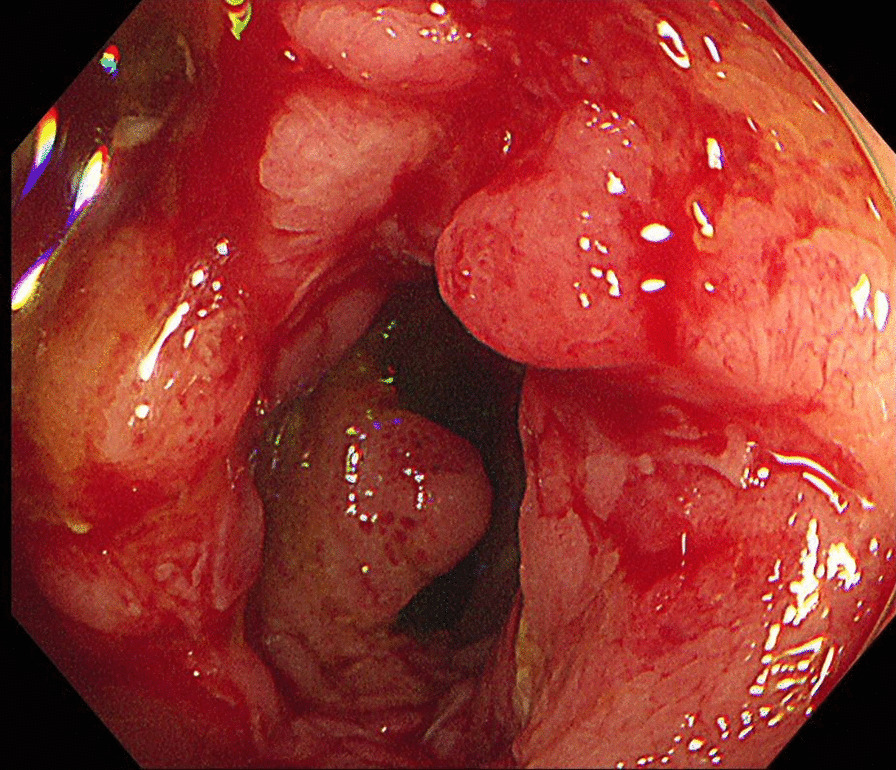

Fig. 3.

Crohn’s ulcers on colonoscopy. Multiple ulcers were seen on terminal ileum mucosa

The patient was then referred to the pediatric gastroenterology department where she underwent further blood tests, gastroduodenoscopy, and colonoscopy to rule out other differential diagnoses, such as sarcoidosis, pyoderma gangrenosum, hiradenitis suppurativa, cellulitis, tuberculosis, and contact dermatitis. Stool calprotectin levels was elevated to > 300 µg/g, which suggested a diagnosis of inflammatory bowel disease. A more detailed history revealed that the patient had no history of diarrhea or hematochezia. On gastroduodenoscopy, gastric mucosa was noted to be erythematous which was suggestive of reflux esophagitis and chronic superficial gastritis. Colonoscopy revealed multiple ulcers on the mucosa of the terminal ileum and the rectum (Fig. 3). Pathological evaluation of tissue specimen retrieved showed mild chronic superficial gastritis and ulceration with ill-defined noncaseating granulomatous lesions in the mucosa of the terminal ileum, which were consistent with a diagnosis of Crohn’s disease or tuberculosis. Further AFB staining and Tb-PCR performed on biopsy samples taken from the terminal ileum were negative, which ruled out tuberculosis. The rectal biopsy specimen was within normal limits. The simple endoscopic score for Crohn’s disease was 11 [13]. The result of the stool culture was positive for Clostridium difficile and the patient received oral metronidazole therapy.